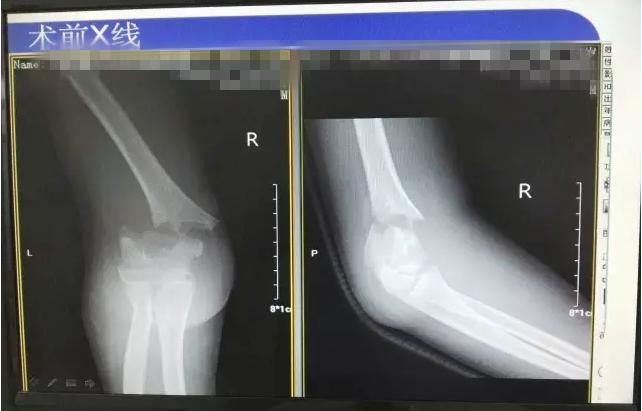

病案二:患儿谭XX,男,14岁,摔伤后右肘关节疼痛伴活动受限5小时入院。

肱骨髁上骨折闭合复位手术记录,小儿肱骨髁上骨折手术恢复的概率 诊断:Gartland III型骨折

肱骨髁上骨折闭合复位手术记录,小儿肱骨髁上骨折手术恢复的概率

术后长臂石膏维持屈肘中立位固定